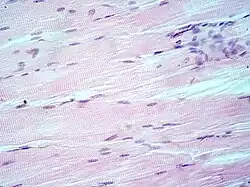

- Muscle tissue, cell nuclei (blue-purple), cell body (pink)

Hematoxylin principally colors the nuclei of cells blue or dark-purple,[6][15][14] along with a few other tissues, such as keratohyalin granules and calcified material. Eosin stains the cytoplasm and some other structures including extracellular matrix such as collagen[5][7][14] in up to five shades of pink.[8] The eosinophilic (substances that are stained by eosin)[5] structures are generally composed of intracellular or extracellular proteins. The Lewy bodies and Mallory bodies are examples of eosinophilic structures. Most of the cytoplasm is eosinophilic and is rendered pink.[10][15] Red blood cells are stained intensely red.

H&E is the combination of two histological stains: hematoxylin and eosin. The hematoxylin stains cell nuclei a purplish blue, and eosin stains the extracellular matrix and cytoplasm pink, with other structures taking on different shades, hues, and combinations of these colors.[5][6] Hence a pathologist can easily differentiate between the nuclear and cytoplasmic parts of a cell, and additionally, the overall patterns of coloration from the stain show the general layout and distribution of cells and provides a general overview of a tissue sample's structure.[7] Thus, pattern recognition, both by expert humans themselves and by software that aids those experts (in digital pathology), provides histologic information.